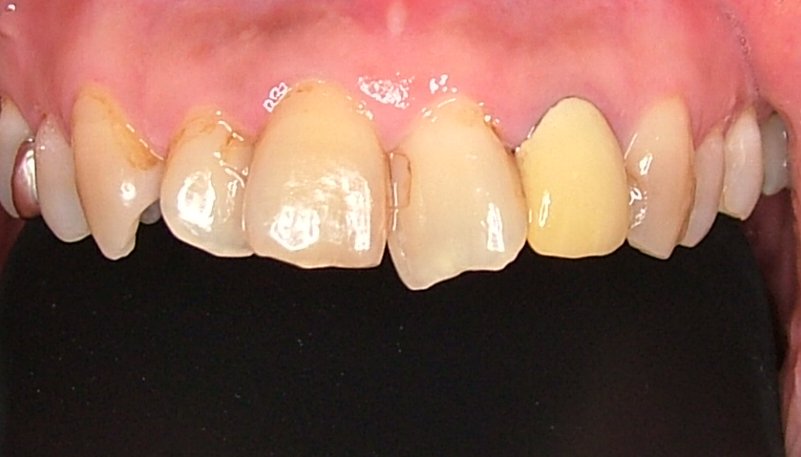

初診時 |

口腔内写真 |

| 治療内容 | 掌蹠膿疱症、不定愁訴も治したい。花粉症もあり。ガルバニー電流測定、オリゴスキャン検査、ビタミンDの血中濃度測定 |

|---|---|

| 治療期間・回数 | 5か月・30回 |

| 治療時の費用 | 1,200,000円(メタルフリー代、サプリメント代) ※本症例当時の価格です。最新の費用はこちら |

| リスク・副作用 | 金属除去後に熱が出たそうですが、一時的な好転反応と思われます。このような症状は個人差があるので、特に心配はありません。 |